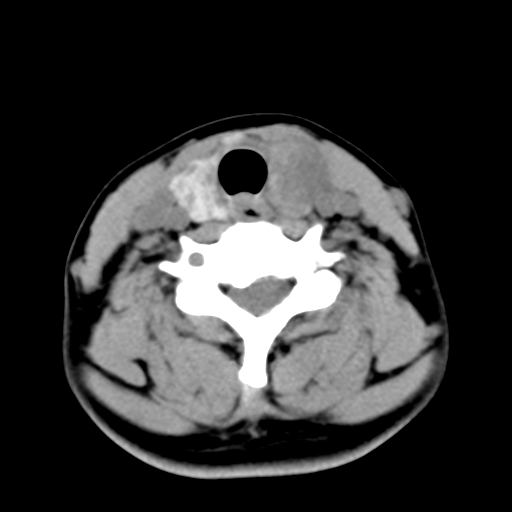

女,44岁,左颈部肿块伴疼痛两个月。患者不能做增强扫描。

左侧甲状腺明显肿大,密度不均匀性减低,正常之钙化基本消失,残留少许呈云雾状及颗粒状。其边缘不规则、不清晰,与前部联合处正常甲状腺不能分界不清,但尚可与周围其他组织分辨。颈动脉鞘区无明显淋巴结肿大。

多考虑:左侧甲状腺癌。

左侧甲状腺腺瘤或癌。甲状腺周围软组织间隙尚存在,喉软骨未见破坏征象,考虑腺瘤可能性大。

左侧甲状腺明显肿大,密度不均匀性减低,可见明显淋巴结肿大.

考虑:左侧甲状腺癌